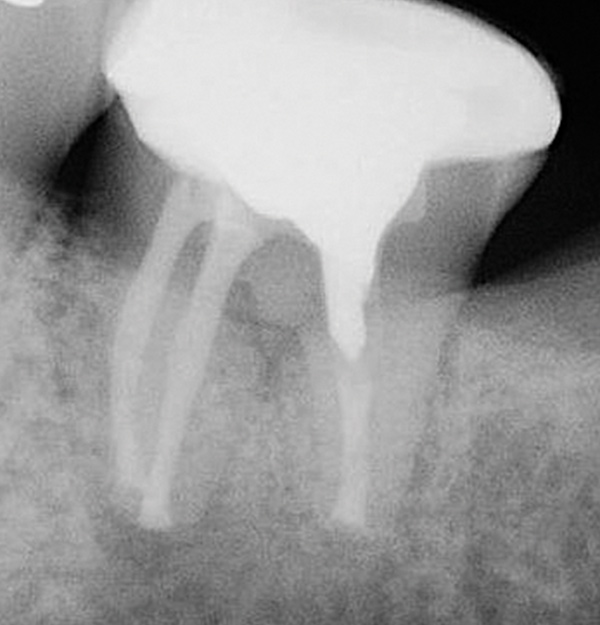

CBCT can be used to aid in further assessment of a previously endodontically treated tooth. A study by Uraba et al demonstrated that CBCT imaging is 20% more effective in detecting periapical lesions that cannot be detected on a periapical radiograph (Figure 1 and Figure 2).7 Diagnostic CBCT can provide additional information in comparison to periapical radiographs when treatment planning an endodontic retreatment case.8 The use of a limited field of view (FOV) CBCT on a patient that presents with a problem on an existing endodontically treated tooth can allow the clinician to critically evaluate the quality of the existing canal(s) obturation, identify any missed canals, and assess the extensiveness of a periapical lesion.

Periapical radiograph of tooth N o. 14 does not definitively reveal

a periapical radiolucency.

Fig 1.

CBCT of the same tooth N o. 14 (palatal

view exposure) shown in Fig 1 definitively shows a periapical lesion.

Fig 2.